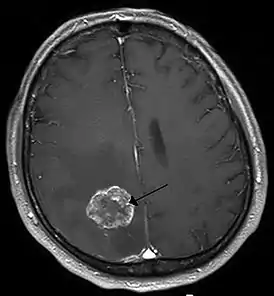

Опухоль головного мозга визуализированная с помощью МРТ - 26 мая 1803 г. профессоор Е. О. Мухин провёл в Москве в Голицынской больнице первую в истории России успешную нейрохирургическую операцию[2]. В 1807—1808 гг. в Санкт-Петербурге было издано оригинальное «Руководство к преподаванию хирургии» И. Ф. Буша. В разделе «О повреждениях черепа» автор рекомендовал производить рассечение раны мягких тканей c удалением мелких свободно лежащих костных фрагментов, инородных тел и сгустков крови; крупные костные фрагменты рекомендовалось трепанировать, обнаруженным внутричерепным кровоизлияниям «давать выход». Выполнение собственно трепанации, то есть расширения имевшегося костного дефекта, рекомендовалось только при наличии симптомов сдавления мозга, к каковым относились головная боль, судороги, воспаление и лихорадка и при больших кровоизлияниях — сужение зрачка, замедление пульса и нарушения дыхания.